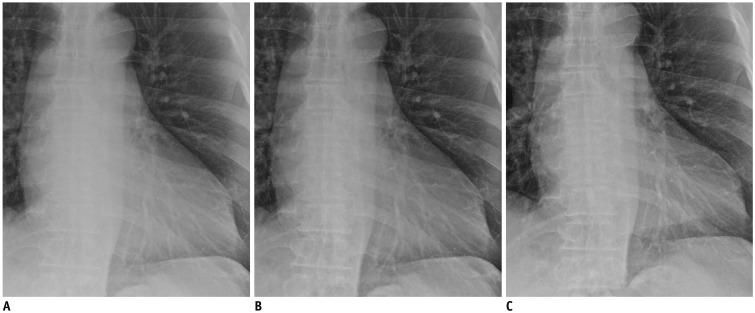

Each of the 38 patients underwent bedside chest radiography with and without a grid. A grid-like image was generated from a non-grid image using SimGrid software (Samsung Electronics Co. Ltd.) employing deep-learning-based scatter correction technology. Two readers recorded the preference for 10 anatomic landmarks and the overall appearance on a five-point scale for a pair of non-grid and grid-like images, and a pair of grid-like and grid images, respectively, which were randomly presented. The dose area product (DAP) was also recorded. Wilcoxon's rank sum test was used to assess the significance of preference.

Both readers preferred grid-like images to non-grid images significantly ( < 0.001); with a significant difference in terms of the preference for grid images to grid-like images ( = 0.317, 0.034, respectively). In terms of anatomic landmarks, both readers preferred grid-like images to non-grid images ( < 0.05). No significant differences existed between grid-like and grid images except for the preference for grid images in proximal airways by two readers, and in retrocardiac lung and thoracic spine by one reader. The median DAP were 1.48 (range, 1.37-2.17) dGycm in grid images and 1.22 (range, 1.11-1.78) dGycm in grid-like images with a significant difference ( < 0.001).

The SimGrid software significantly improved the image quality of non-grid images to a level comparable to that of grid images with a relatively lower level of radiation exposure.